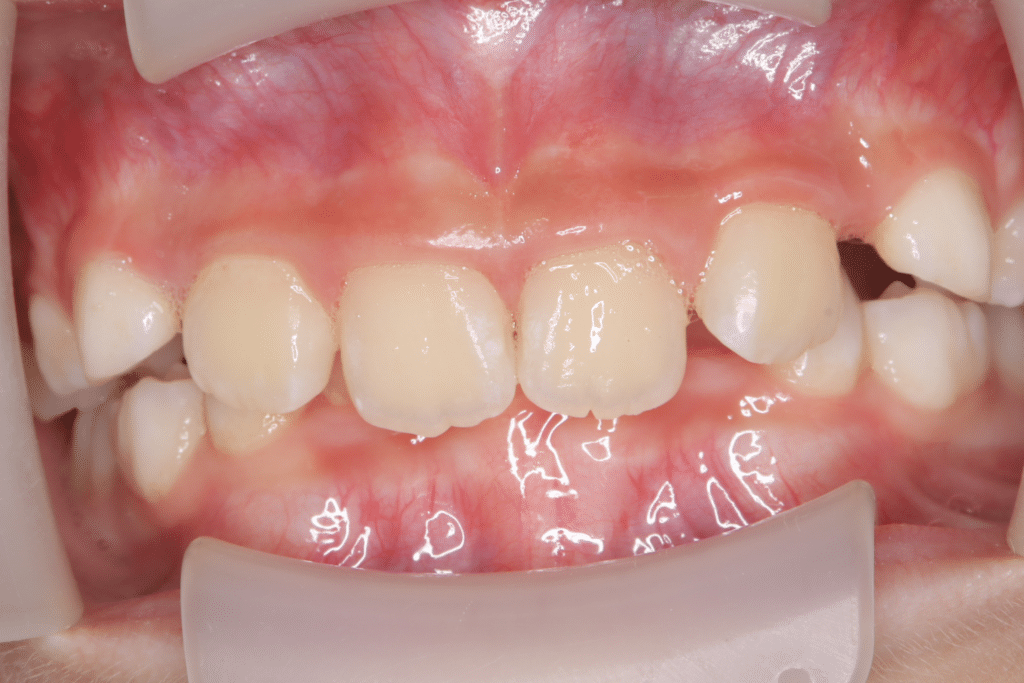

過蓋咬合

(9歳2ヶ月)

開始後0ヶ月

(開始後0ヶ月)噛み合わせの深さからくる咬合圧の強さと歯ぎしりを心配されていたため、歯ぎしりから歯を守りつつ、噛み合わせの深さを改善するためのマウスピースを使用開始。

いくつか方法がある中で、今回は保護者と患児の希望も含めて、過蓋咬合専用のマウスピースと、筋機能療法を併用し、顎の噛み合わせの深さを改善する方向で進めるプランで合意した。